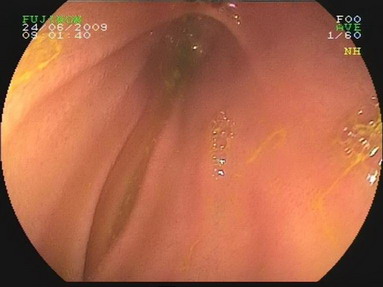

2009.6.24胃镜:

慢性浅表性胃炎,十二指肠淤滞症原因待查,肠系膜上动脉压迫综合症?(胃内可见胆汁样物反流,十二指肠球扩张,降部明显扩张,水平部远端似可见狭窄,持续充气肠腔不能打开。)